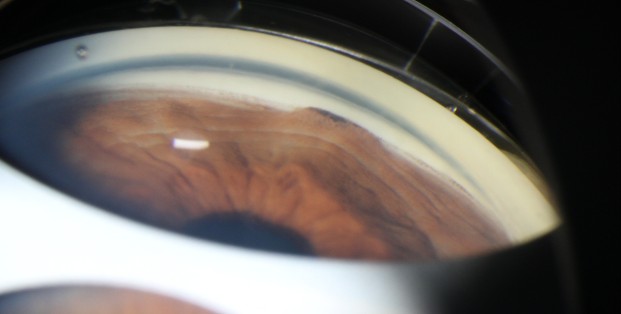

Gonioscopie of studie van de voorste oogkamer vormt een belangrijk onderdeel van de glaucoomdiagnose en -behandeling. De voorste oogkamer is niet direct te onderzoeken en door middel van een gonioscoop is de hoek te visualiseren. Er worden verschillende soorten gonioscopen gebruikt om te helpen bij de diagnose en het management.

Tijdens dit webinar komen de volgende elementen aan bod: welke lens wordt wanneer gebruikt en waarom, hoe is de kamerhoek opgebouwd (welke structuren zie je), hoe wordt het onderzoek uitgevoerd (systematische benadering), welke notatiemethoden zijn er (welke classificatie wordt wanneer gebruikt waarom) en welke conclusies kunnen er verbonden worden aan alle bevindingen. Aan het einde van het webinar is uw kennis op het gebied van anatomie, pathologie en glaucoommanagement weer opgefrist.